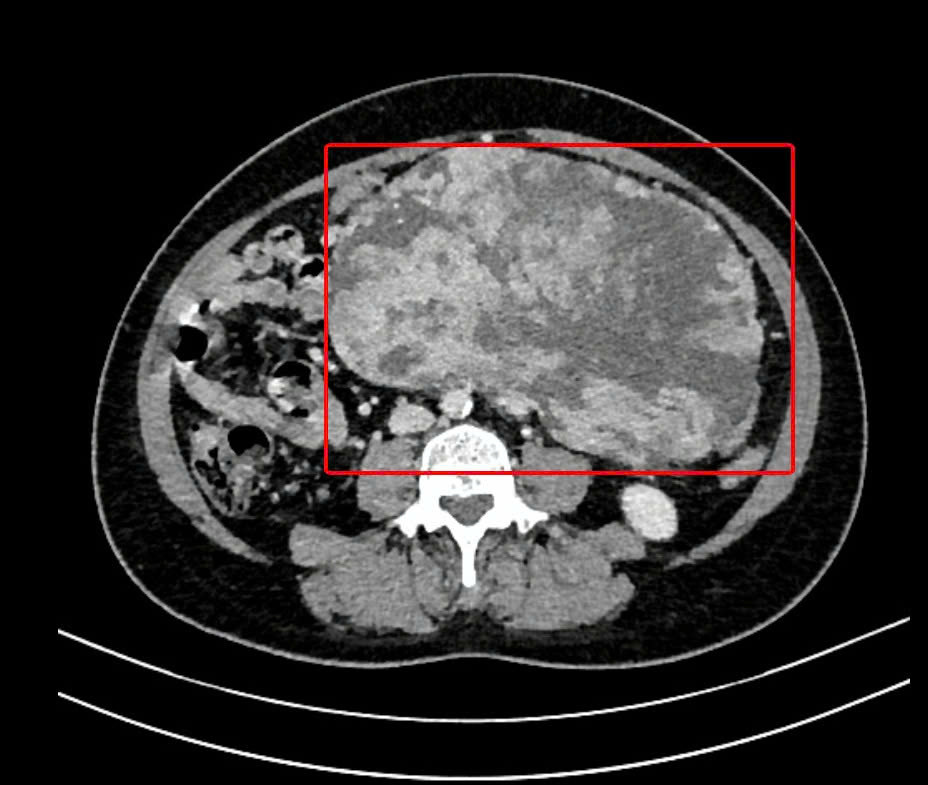

| Hình ảnh kiểm tra ghi nhận khối u có kích thước rất lớn chiếm gần trọn thể tích ổ bụng bệnh nhân |

Qua các kết quả xét nghiệm, kiểm tra hình ảnh, các bác sĩ chẩn đoán bệnh nhân có khối u kích thước lên tới 20x18x13cm chiếm khoảng 60% thể tích ổ bụng, chèn ép các tạng phủ. Các bác sĩ nghi ngờ bệnh nhân bị u mô đệm đường tiêu hóa (GIST). Đây là dạng u hiếm gặp có tính chất ác tính, phát triển trong thành của hệ thống ống tiêu hoá xuất phát từ dạ dày.